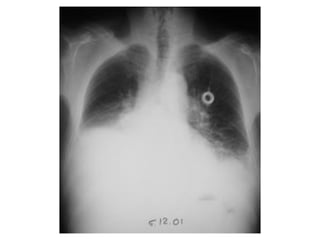

Pneumothorax incomplet gauche